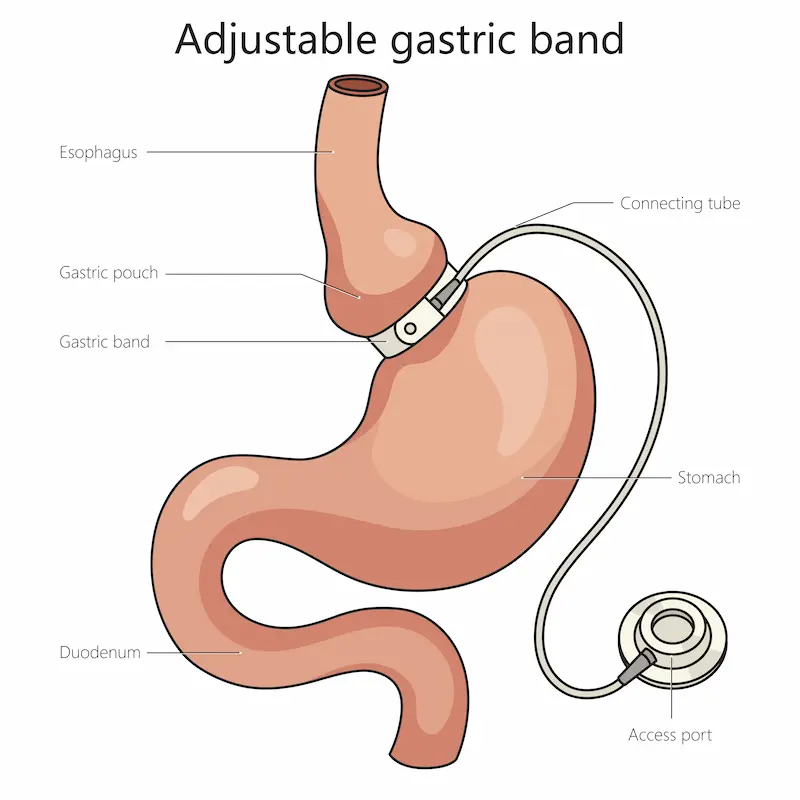

Основная идея процедуры — создание небольшого «нового» желудка объемом всего 15–20 мл в верхней части органа. Это достигается путем установки специального силиконового кольца — бандажа. Когда этот маленький резервуар наполняется пищей, рецепторы насыщения, расположенные именно в этой зоне, мгновенно посылают в мозг сигнал «я сыт». В результате чувство голода утоляется гораздо меньшим количеством еды, а ощущение сытости сохраняется значительно дольше. Таким образом, пациент начинает есть реже и меньшими порциями, что приводит к стабильному и безопасному снижению веса.

Ключевой вывод: Желудочный бандаж работает по рестриктивному принципу, то есть он ограничивает количество съедаемой пищи, а не нарушает процесс ее всасывания. Это позволяет избежать многих проблем, связанных с дефицитом витаминов и минералов, которые характерны для других, более инвазивных бариатрических операций. Именно поэтому многие пациенты, стремящиеся как безопасно похудеть, выбирают установку бандажа на желудок как наиболее физиологичный метод хирургического лечения ожирения. Этот метод не требует резекции (удаления) частей органов и не меняет естественный путь пищи по желудочно-кишечному тракту.

Еще одно уникальное преимущество — возможность регулировки. Регулируемый желудочный бандаж соединен тонкой трубкой с небольшим портом, который имплантируется под кожу брюшной стенки. Через этот порт хирург может вводить или удалять стерильный физиологический раствор, тем самым изменяя внутренний диаметр кольца. Это позволяет «настраивать» скорость похудения, адаптируясь к потребностям и самочувствию пациента на разных этапах послеоперационного ухода. Если вес уходит слишком быстро или, наоборот, медленно, врач может легко скорректировать степень сужения желудка, добиваясь оптимальных результатов. Эта гибкость делает бандажирование желудка в Турции персонализированным инструментом в борьбе с лишним весом.

- Формирование «малого желудочка»: Хирург аккуратно проводит регулируемый желудочный бандаж вокруг верхней части желудка, создавая над ним небольшой резервуар объемом около 20 мл.

- Фиксация бандажа и порта: Кольцо надежно фиксируется несколькими швами, чтобы предотвратить его смещение. Соединенный с бандажом порт для регулировки имплантируется под кожу в легкодоступном месте на животе.

Процедура регулировки очень проста и занимает всего несколько минут. Она проводится амбулаторно и не требует анестезии. Врач с помощью тонкой иглы находит под кожей порт и вводит в него или откачивает из него небольшое количество стерильного физраствора. Добавление жидкости сужает просвет бандажа, усиливая ограничение. Удаление жидкости — ослабляет его. Цель — найти идеальный баланс, при котором вы будете худеть на 0.5-1 кг в неделю, не испытывая дискомфорта, тошноты или рвоты.